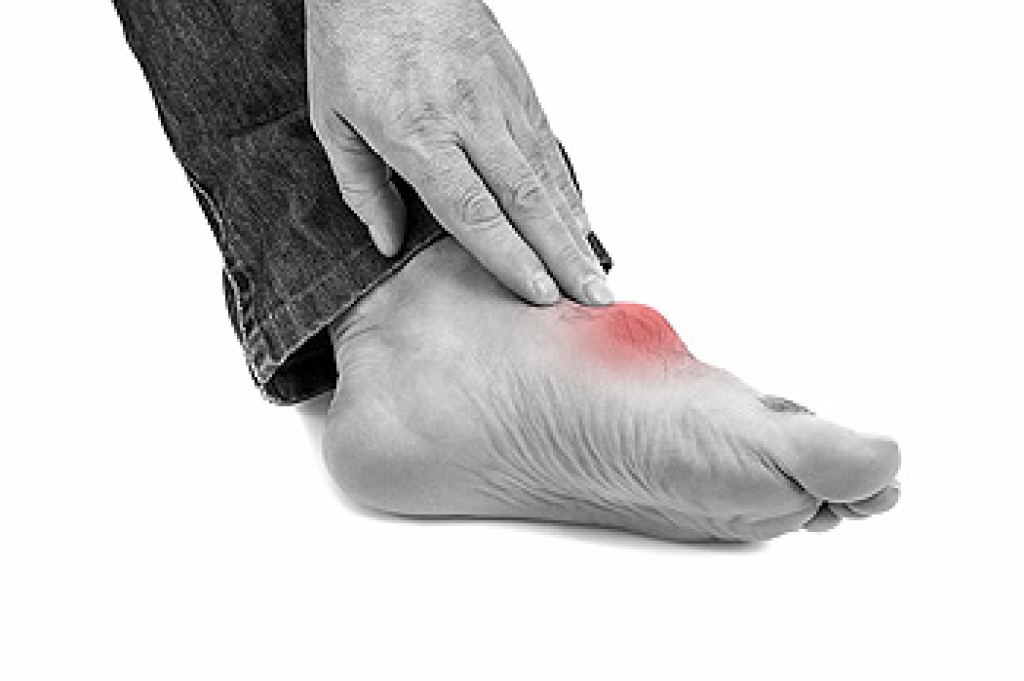

Gout, often referred to as the disease of kings, is a form of inflammatory arthritis that has affected individuals from all walks of life. This condition, caused by the accumulation of uric acid crystals in the joints, typically manifests as excruciating pain, swelling, and redness, often in the big toe. The pain can be so intense that even the touch of a bedsheet can trigger agony. Gout occurs when the body produces excessive uric acid or struggles to eliminate it efficiently, leading to the formation of sharp crystals within the joints. While it primarily targets the feet, gout can also affect other joints, such as the ankles, knees, and wrists. Dietary choices, genetics, obesity, and other medical conditions can contribute to gout's onset. Understanding this ailment is essential for individuals who suffer from it and for those seeking to support them in their journey to manage gout effectively. Gout can affect daily activities, and if you are afflicted with this form of arthritis, it is strongly suggested that you are under the care of a podiatrist who can help you manage this condition.

Gout can easily be identified by redness and inflammation of the big toe and the surrounding areas of the foot. Other symptoms include extreme fatigue, joint pain, and running high fevers. Sometimes corticosteroid drugs can be prescribed to treat gout, but the best way to combat this disease is to get more exercise and eat a better diet.